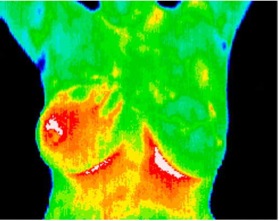

The thermal imaging uses physiologic changes– increased blood flow to the cancers– to find abnormal growth. Since these changes occur before the tumor is large enough to be found by a mammogram, thermography can find cancers well before they can be picked up my mammograms.

The image on the right is an inflammatory breast cancer that had no symptoms and would not show up on a mammogram.